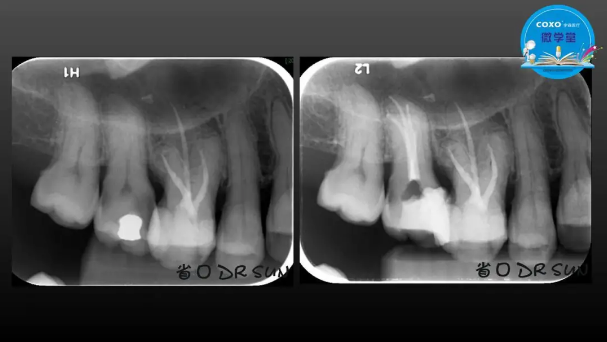

主講:孫書昱

主任醫(yī)師,牙體牙髓副主任, 廣東省口腔醫(yī)院牙體牙髓科 主任醫(yī)師。2003年碩士研究生畢業(yè),研究方向為牙體牙髓病學,擅長于牙體牙髓病的診斷、齲齒、牙髓炎、根尖周病的治療以及前牙美容修復。